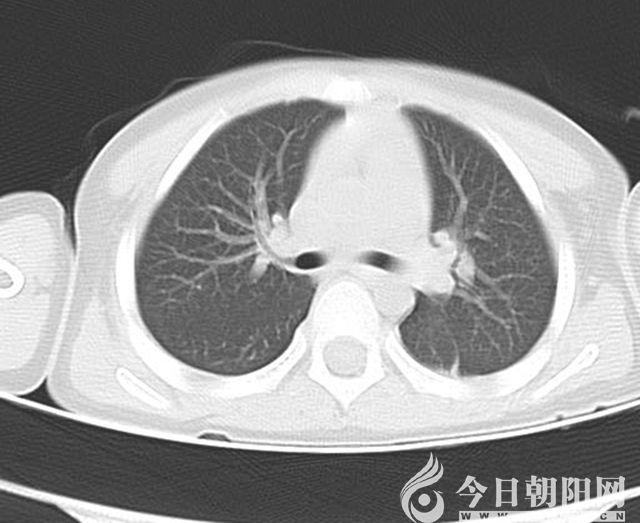

做鏡前肺CT

7月5日,一名4歲大的男孩兒,因“發(fā)熱7天,咳嗽3天”來到朝陽市第二醫(yī)院兒科就診。入院時,患兒精神狀態(tài)差,呻吟,無鼻翼扇動,可見輕度三凹征,左肺呼吸音較右側(cè)減弱;肺CT顯示左肺炎性病變,左肺下葉膨脹不良。通過檢查,診斷為重癥肺炎、胸腔積液、膿毒血癥、支原體感染,給予4代抗生素抗感染及抗支原體治療。住院第5天,復(fù)查肺CT顯示左肺下葉膨脹不良無明顯改善,考慮存在痰栓堵塞,立即進行纖維支氣管鏡檢查+支氣管肺泡灌洗術(shù)治療,灌洗過程中吸出塑形性痰栓多量。術(shù)后第6天復(fù)査肺CT,左肺上葉片影消失,左肺下葉膨脹不良明顯改善。7月19日,患兒出院。7月末,男孩兒來到醫(yī)院復(fù)査,肺CT顯示炎癥基本吸收。